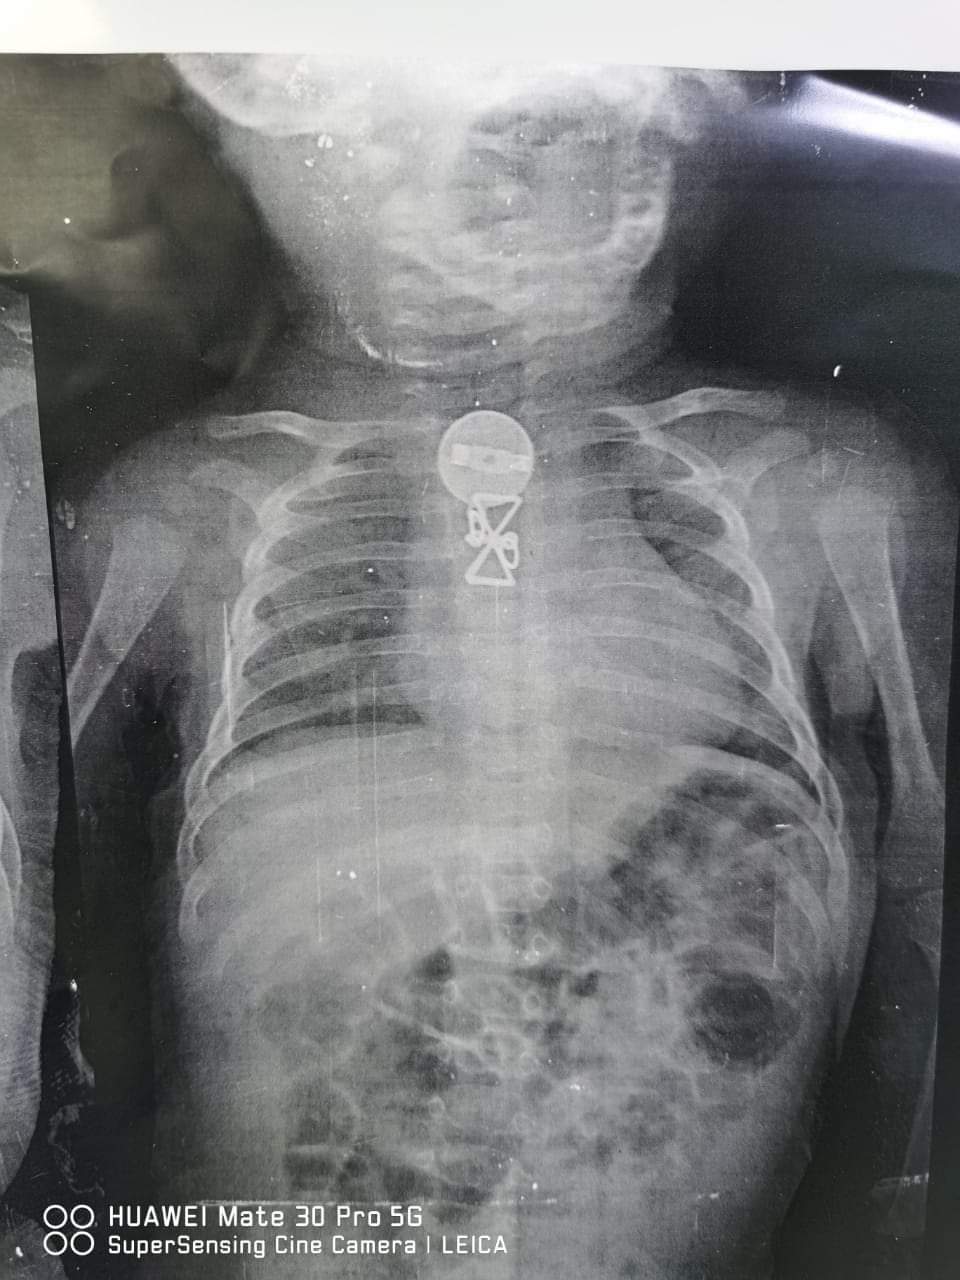

نجح فريق طبي بمستشفى الأطفال التخصصي ببنها، برئاسة الدكتور محمد محمد متولي استشاري جراحة الأطفال في استخراج جسم غريب من طفل يبلغ من العمر ثلاثة أشهر.

وأشار رئيس الفريق الطبي، في بيان صدر اليوم، إلى أن المستشفى استقبل الطفل وكان يعاني من ضيق في التنفس وتم حجزه بالمستشفى وعمل الإشاعات اللازمة وتبين وجود جسم معدني داخل الجسد واستخراجه، وتم العرض على والديه الذين أقروا أن شقيقته الكبرى كانت تداعبه وبلع تلك الجسم المعدني منذ فترة.